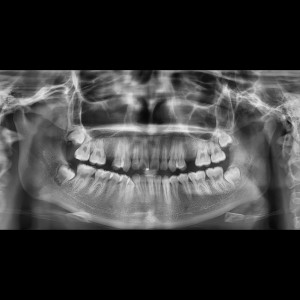

SERVICIOS 2D

SIALOGRAFIA